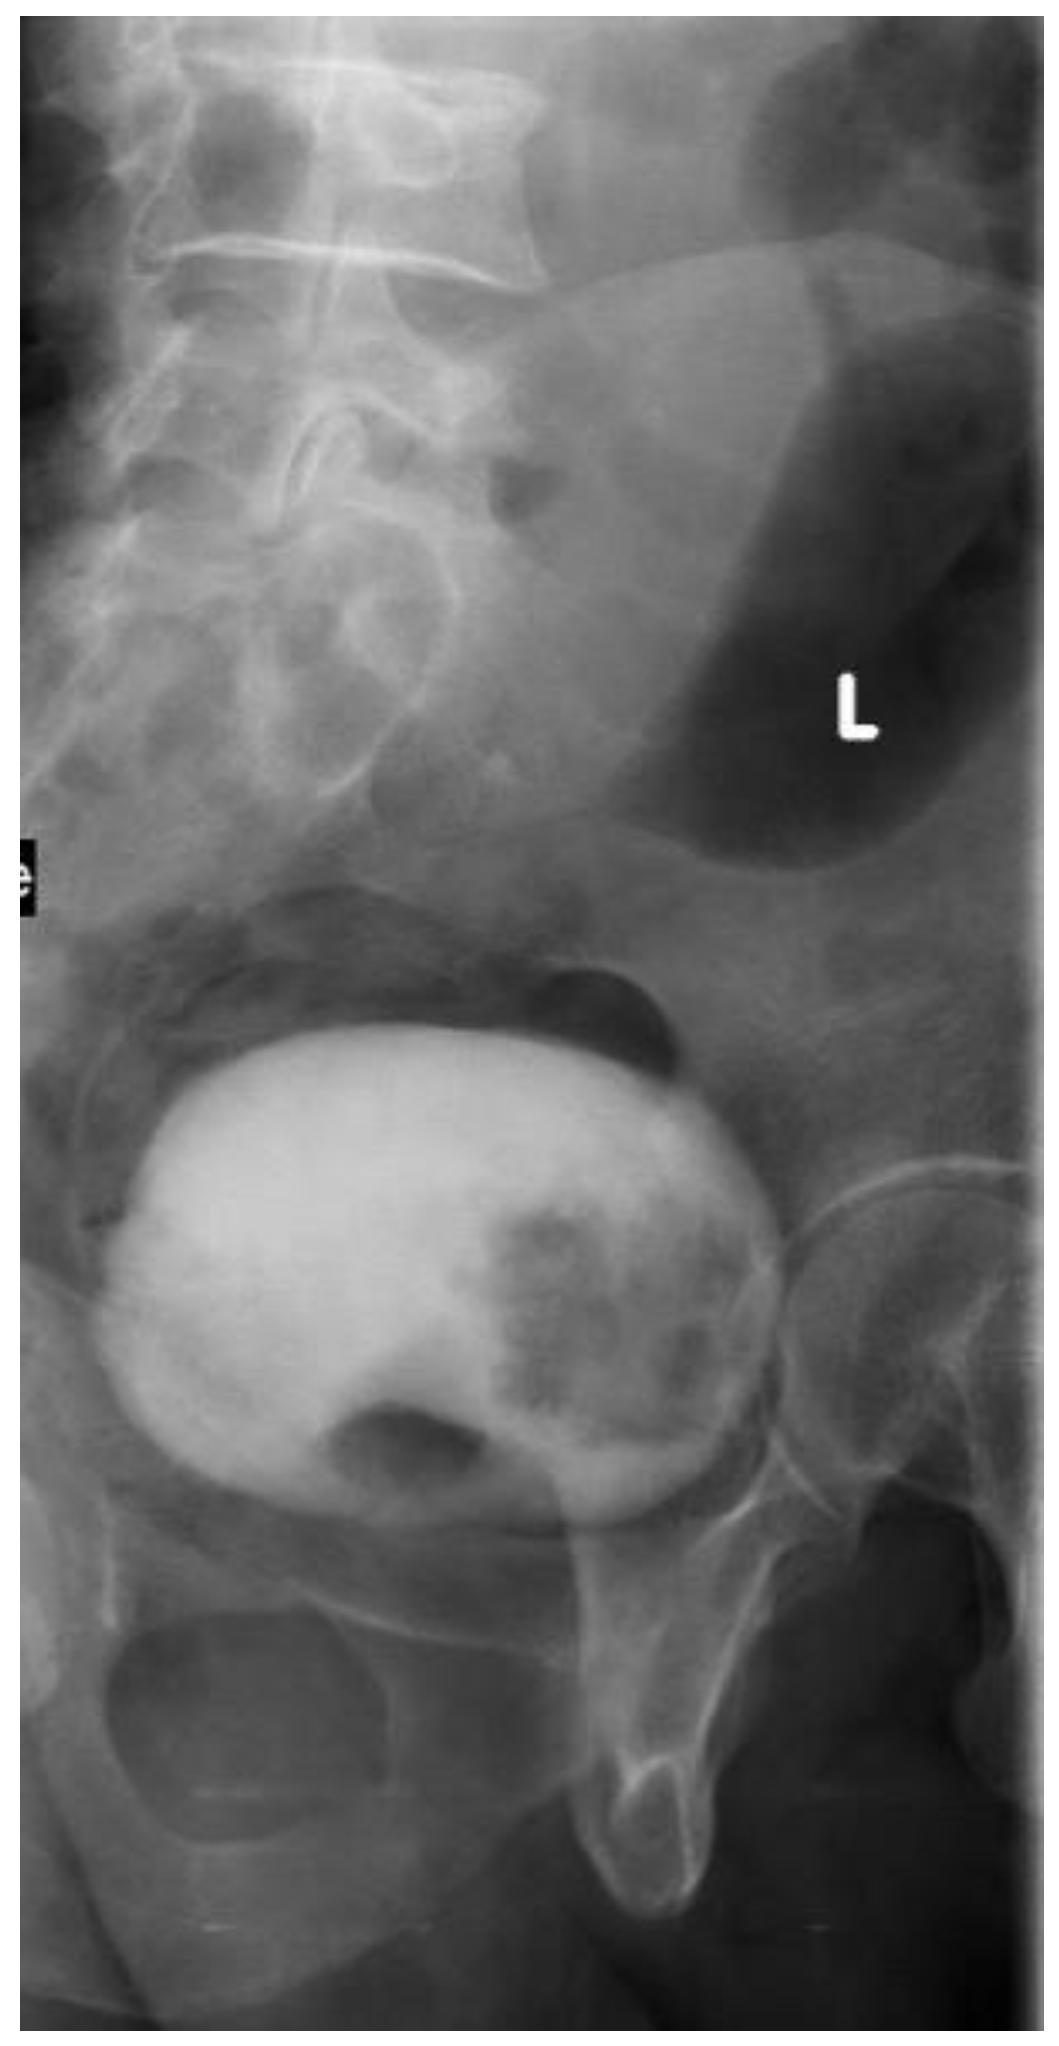

2.2. Intravenous Urography “IVU”

- Rafique, M.; Javed, A.A. Role of intravenous urography and transabdominal ultrasonography in the diagnosis of bladder carcinoma. Int. Braz. J. Urol. 2004, 30, 185–190, discussion 191. [Google Scholar] [CrossRef] [PubMed]